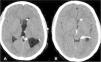

La derivación ventrículo biliar se describe como un procedimiento alternativo eficaz en el tratamiento de la hidrocefalia. Presentamos el caso de un paciente de 19 años de edad diagnosticado de quiste aracnoideo supraselar e hidrocefalia, portador de doble sistema valvular de derivación ventrículo peritoneal y cisto peritoneal desde la infancia. Tras varios recambios por fallo peritoneal, fue sometido a derivación ventriculoauricular, con complicaciones asociadas y posterior recolocación a peritoneo. Tras nueva disfunción valvular por complicaciones peritoneales, se planteó la derivación ventriculobiliar como tratamiento alternativo para este paciente, que resultó segura y eficaz en la resolución de la clínica del paciente, siendo dado de alta, manteniendo estabilidad clínica durante más de 2años de seguimiento.

Ventriculo-gallbladder shunt is described as an effective alternative procedure in the treatment of hydrocephalus. We present the case of a 19-year-old patient diagnosed with suprasellar arachnoid cyst since his childhood and hydrocephalus, with a double shunt; ventriculoperitoneal and peritoneal cyst shunt. After several replacements due to peritoneal failure, he underwent ventriculoatrial shunt, with associated complications and subsequent repositioning to the peritoneum. After new valve dysfunction due to peritoneal complications, ventriculo-gallbladder shunt was proposed as an alternative treatment for this patient, which was safe and effective in resolving the patient's symptoms, and the patient was discharged, maintaining clinical stability in the follow-up more than 2 years later.